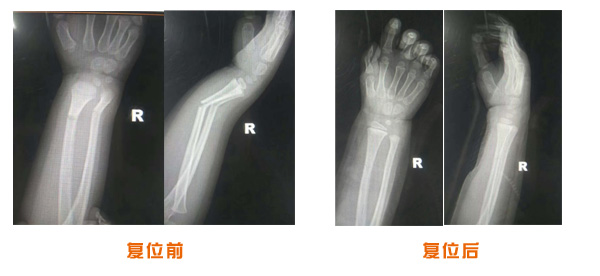

肘關節脫位骨折治療前后對比

踝關節脫位骨折治療前后對比